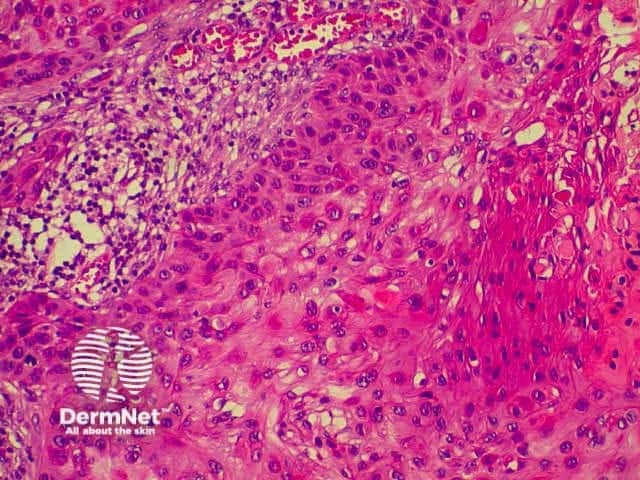

Invasive squamous cell carcinoma (SCC) is characterised by dermal invasion. Link to a clinical description of invasive squamous cell carcinoma.

SCC is characterised by proliferation of irregular nests of abnormal squamous cells arising from the epidermis and invading the dermis. Tumours are traditionally divided into well, moderately or poorly differentiated tumours by a subjective assessment of how significantly the tumour cells differ from normal keratinocytes. In general, the greater the degree of keratinization, the better differentiated the tumour is thought to be. Except in the case of very poorly differentiated tumours, this does not have a great bearing on prognosis. More important is the depth and irregularity of invasion, particularly the presence of perineural infiltration, which is associated with a much higher rate of recurrence if not widely excised. The site of the lesion is also important; tumours of the lips and ears have a considerably higher rate of metastasis to lymph nodes.

There are several descriptive variants of SCC including spindle cell SCC and acantholytic (or adenoid or pseudoglandular SCC). These mainly are of note due to the difficulty of diagnosing the tumour as SCC, but they may also imply a slightly worse prognosis. A further rare variant is verrucous carcinoma, a lesion in which the histology has a deceptively benign appearance in that there is very little cytological abnormality. Diagnosis in these cases may be delayed and the diagnosis may not be made until several biopsies have been performed. These tumours recur locally, but do not generally metastasise.

From the above comments it can be seen that the histological features of SCCs can vary, but in general are:

Pathology of SCC Pathology of SCC Pathology of SCC Pathology of SCC